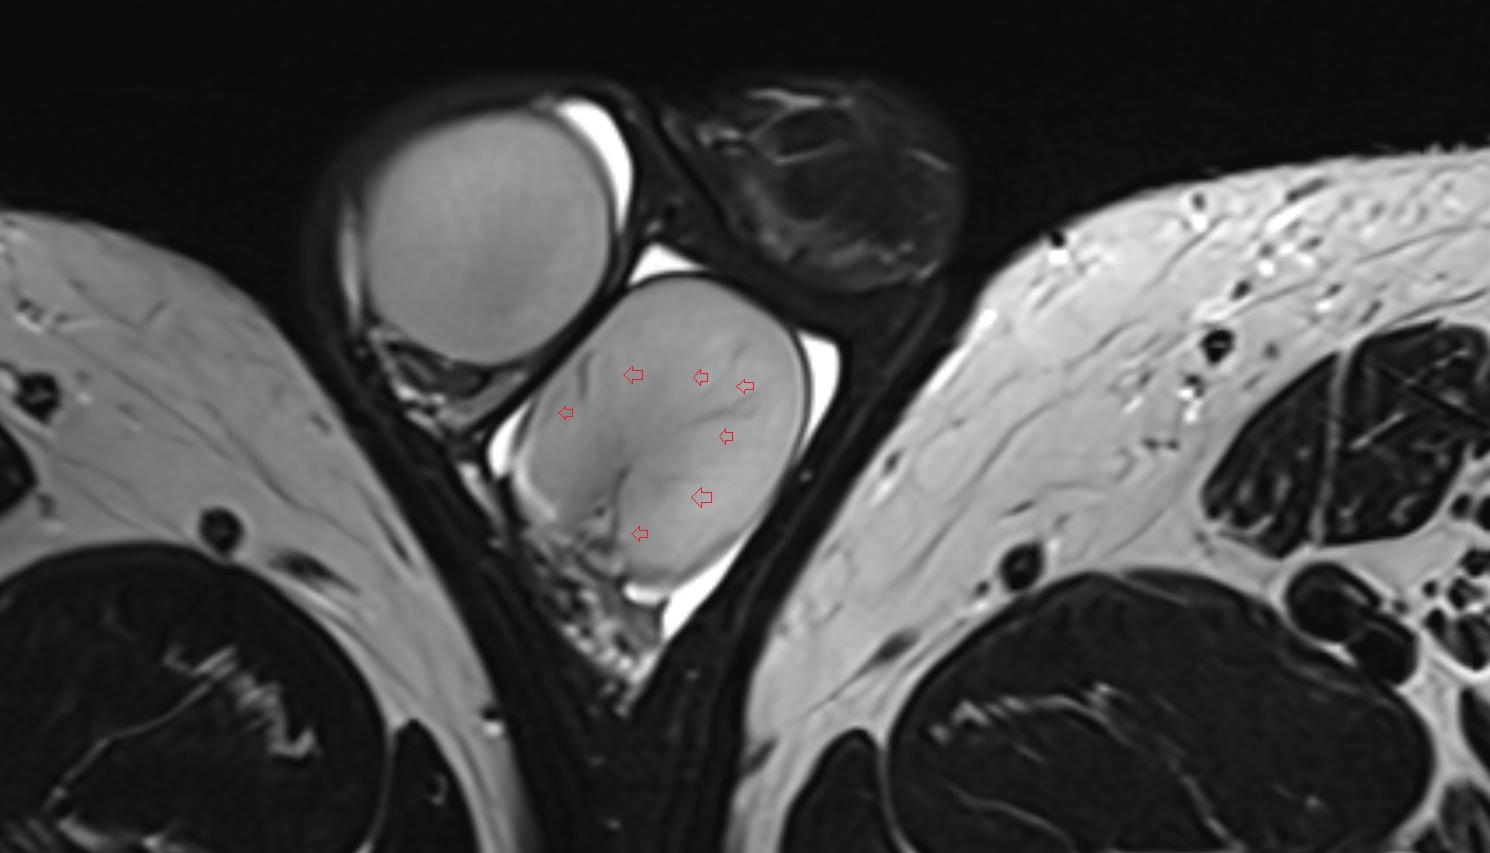

- Peripheral zone of prostate

- Anterior Fibromuscular Stroma of prostate

- Central zone of prostate

- Transitional zone of prostate